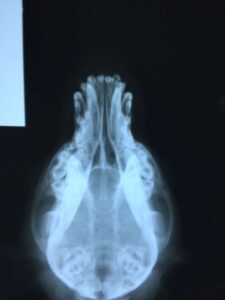

Chavela_9764

Chavela